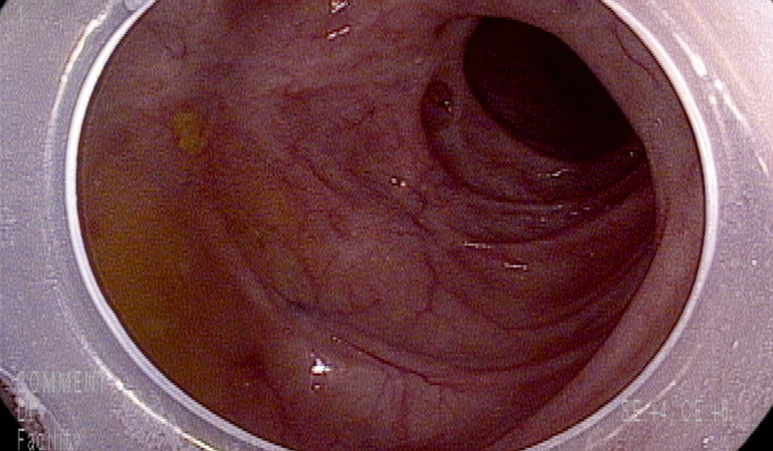

복통과 묽은 변으로 대장내시경 시행

상행결장에 심한 구조 변화, 흉터 변화

소장 말단에는 특이소견은 없으나

회맹판은 열려 있으며 회맹판 경계에 다수의 작은 미란들